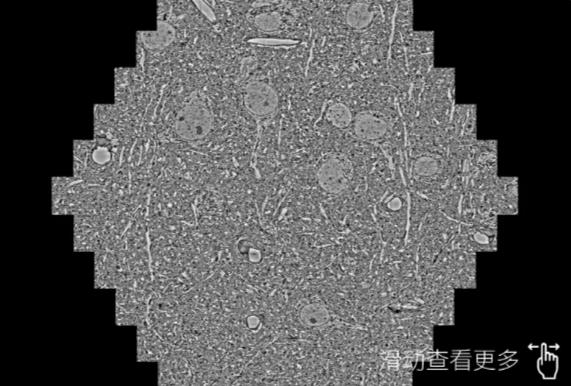

鼠脑切片。左图使用怀柔蔡司怀柔扫描电镜MultiSEM706对165μmx143pm面积区域成像,耗时仅需1.5秒。右图为鼠脑切片中30μm区域放大效果。样品由芝加哥大学B.Kasthuri提供。